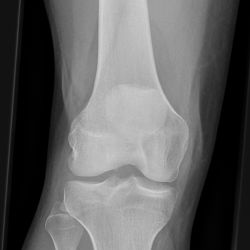

Tibiakopffraktur (nicht disloziert)